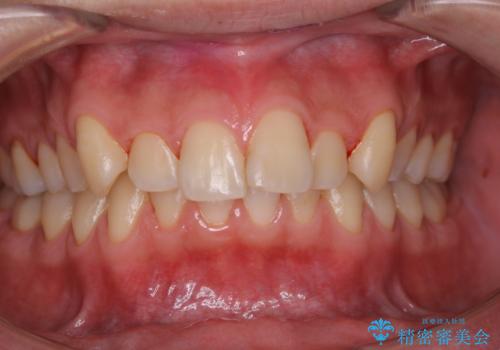

- 矯正治療が始まる前に、クリーニングと歯磨き指導で来院されました。染め出しをして、どこに汚れが残っていないか確認し、ブラッシング指導・PMTC30 分コースを行いました。

口腔内にはたくさんの細菌がいるため、ヌルヌルとしたプラーク(歯垢)が自然に歯の表面に付きます。

このプラーク(歯垢)にはたくさんの細菌が潜んでおり、虫歯や歯周病・口臭などの最大の原因です。そのため、毎日の歯磨きでプラーク(歯垢)をキレイに取り除くことが、健康な歯を保つためには欠かせません。